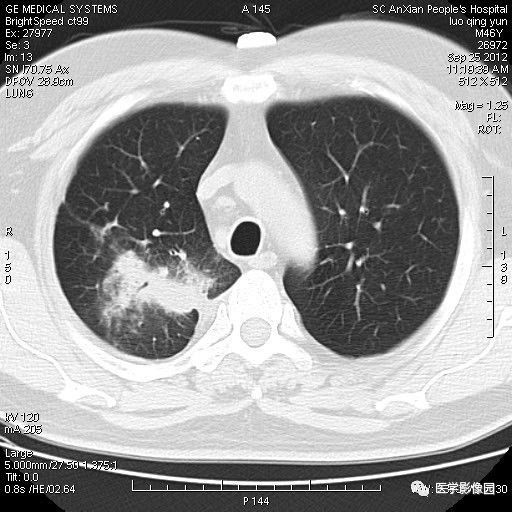

【病例】右上肺炎性假瘤1例CT影像表现

患者男性,46岁,临床未提供病史。

影像学表现:右上肺见不规则团块状高密度阴影,略有分叶级毛刺,边缘模糊,邻近胸膜增厚,增强扫描呈轻中度强化。

诊断结果:右上肺炎性假瘤

本病影像学表现无绝对特征性。单发多见,多位于肺表浅部位,多呈圆形或椭圆形,直径多在2-5cm或更大;多有假包膜,边缘多清晰光整,有时也毛糙,并可有分叶或毛刺;邻近胸膜局限性增厚、牵拉,病灶边缘呈桃尖样突起即桃尖征(尖端指向胸膜);增强扫描多呈中度均匀强化,持续时间较长。亦可显著强化。